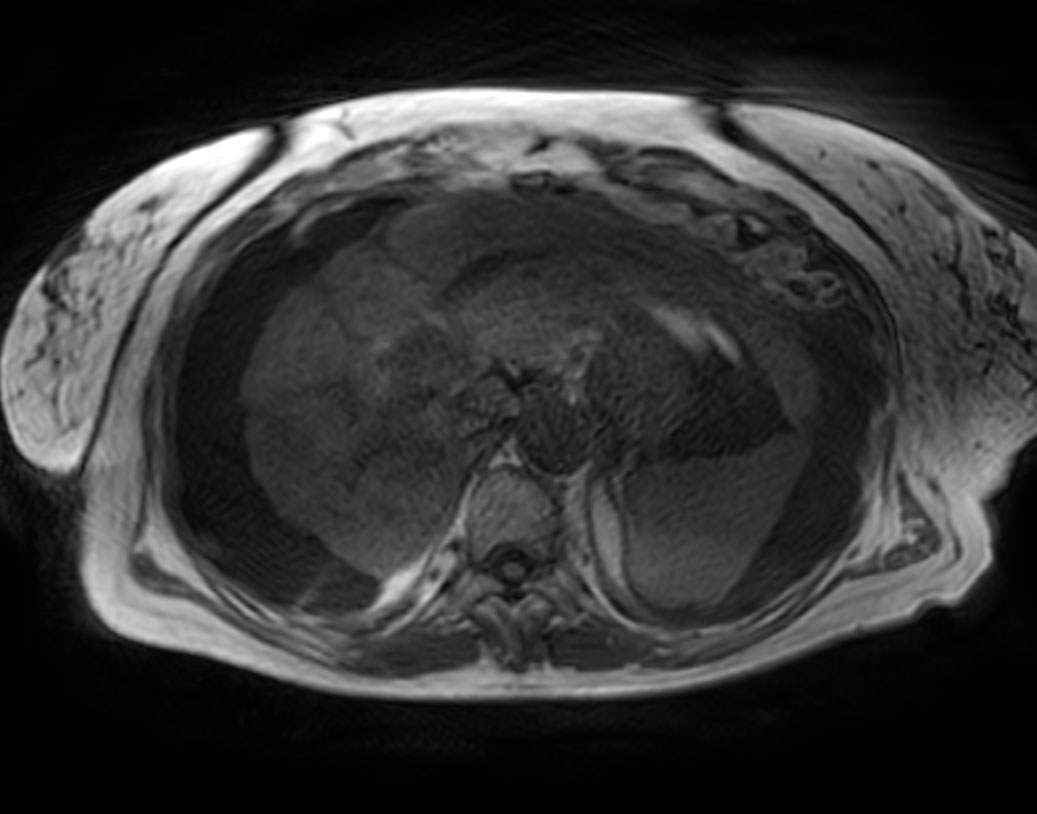

Coronal T2w SSh